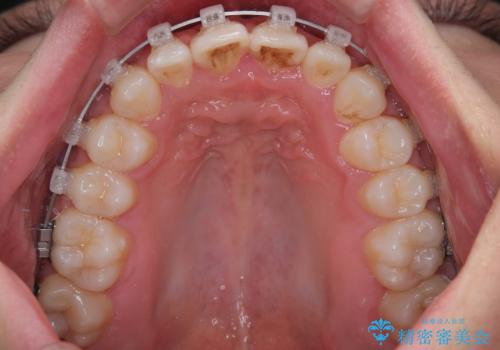

- 矯正装置

- クリアブラケット

そのため今回は、プラスチックブラケット+メタルワイヤーによるクリアブラケットによる治療を選択しました。